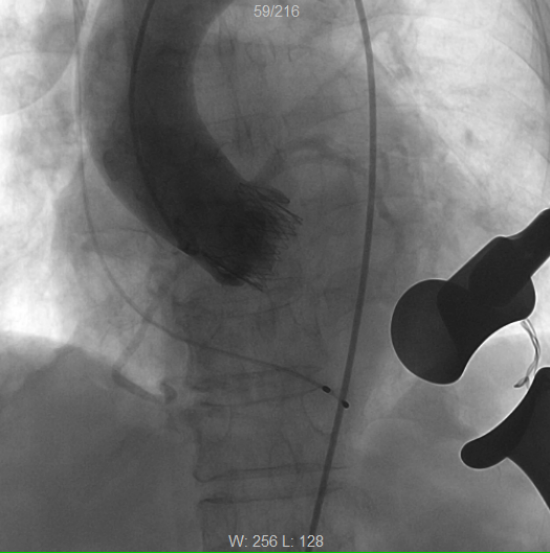

术后再次造影检查,见人工主动脉瓣位置良好,瓣口返流消失